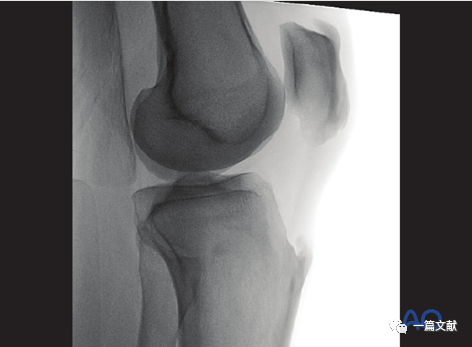

二,标准侧位片

1)体位:稍垫高患侧膝关节,以便透视侧位,下肢于中立位。如下图:

2)标准侧位的评估:1、股骨髁在图像的前方、后方、远端均重叠2、股骨髁位于图像中央 3,C臂机射线平行于胫骨关节面照射。如下图:

3)解剖标志的识别:如下图:1、外侧平台关节面(凸面)2、内侧平台关节面(凹面)3、髁间脊4、胫骨结节5、闭合的骨骺线

4)标准侧位的意义:1、评估内侧和外侧平台复位情况;2、评估胫骨髁间脊复位情况;3、评估胫骨平台是否存在相对于股骨向前或向后的半脱位(表明交叉韧带损伤);4、检视是否存在突入关节的内植物。